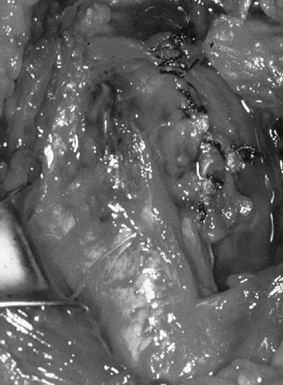

from the severe, unpredictable destruction of both bone and soft

tissue, which is the hallmark of the disease (Fig. 101.51, Fig. 101.52, Fig. 101.53 and Fig. 101.54). Severe medial and superior wear of the

glenoid, cuff defects of varying sizes, poor soft-tissue quality,

associated acromioclavicular joint disease, osteoporosis, and severe

bone loss are among the factors that present technical difficulties (29,36,52).

![]() |

|

Figure 101.51.

Rheumatoid arthritis of the shoulder. Superior migration of the humeral head, cyst formation, marginal erosion, and severe joint destruction. |

Figure 101.52. Rheumatoid arthritis with severe superior and medial destruction of the glenoid.

Figure 101.53.

In this patient with rheumatoid arthritis, there is a fracture of the acromion from superior migration, wear into the acromioclavicular joint, and severe medial migration of the humerus with glenoid bone loss. |

Figure 101.54.

Rheumatoid arthritis with severe bone loss in the proximal humerus. The amount of glenoid bone loss precluded insertion of a glenoid component, and a proximal humeral component alone was used. |